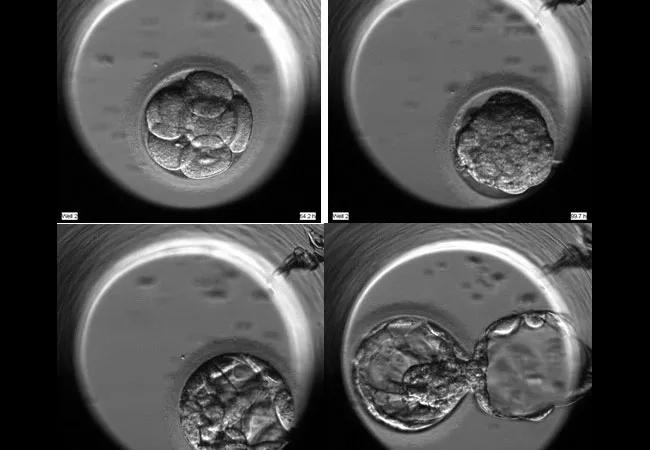

Time-Lapse Images of Embryo Cell Division Are Giving IVF Researchers New Clues

With the EmbryoScope, a specialized culture incubator that contains a time-lapse video camera, scientists have a continuous record of embryo development without ever having to remove embryos from an incubator. This new technology is giving Cleveland Clinic’s IVF laboratory and clinicians greater insight into the kinetic and morphology patterns of individual embryos.

“There’s a lot of information to be gleaned by looking the time-lapse images,” says Nina Desai, PhD, HCLD, of Cleveland Clinic’s Fertility Center. “We’re seeing things we’ve never seen before.”

Dr. Desai and her colleagues recently performed two investigations using those time-lapse video images to look at how embryo cell division rhythms and characteristics might affect embryo chromosomal integrity. One study focused solely on multinucleated embryos (MU) while the other focused on MU, plus embryos with delayed blastulation and cleavage anomalies.